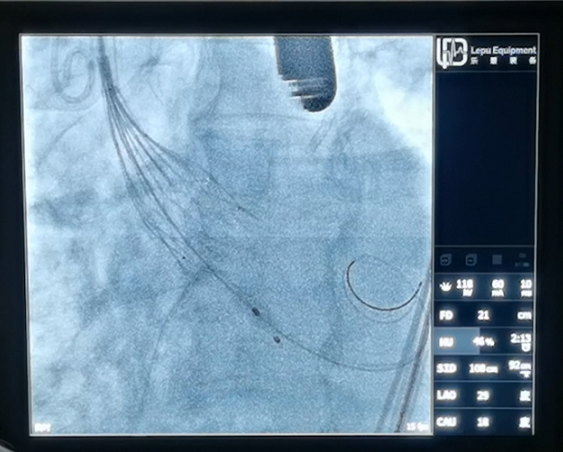

SinoCrown™ 经导管植入式主动脉瓣膜系统由镍钛合金瓣膜支架、牛心包瓣叶和PET内外裙边组成,由乐普(北京)医疗器械股份有限公司自主研发。

这款新型瓣膜系统应用介入导管技术,无需开胸、无需体外循环,创伤小、恢复快,为更多高龄、高危及不能耐受传统外科开胸手术的主动脉瓣疾病患者提供了新的解决方案。

经导管主动脉瓣置换术(TAVR)是一种微创瓣膜置换手术,通过介入导管,将人工心脏瓣膜输送至主动脉瓣位置,从而完成人工瓣膜置入,恢复瓣膜功能。